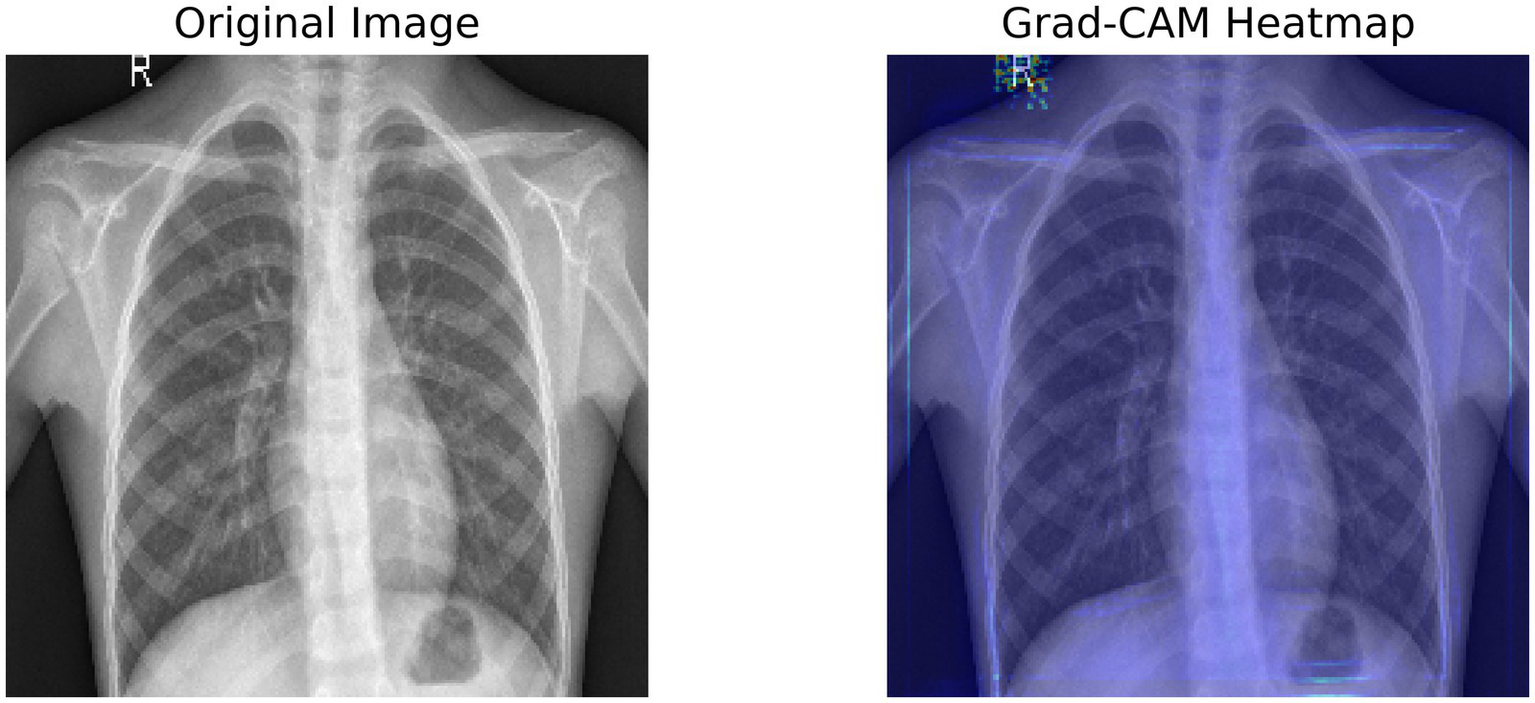

Figure 3 shows a Grad-CAM heatmap applied to a chest X-ray that demonstrates the significant regions identified by the model when predicting. The left image is the original X-ray and the right image is the same X-ray with the Grad-CAM image weights applied to indicate the areas the model activated based on the gradient in the final convolutional layer. The activated regions outlined in the Grad-CAM heatmap images show which areas contribute most to the model’s processes. Interpretability gives a greater level of transparency to deep learning models and enables clinicians to verify AI-generated diagnosis recommendations. The model appears to concentrate on lung regions which adds credibility to its reliability on pneumonia.

Figure 3

Grad-CAM heatmap, highlighting the important regions of the X-ray using the target gradients of the final layer.